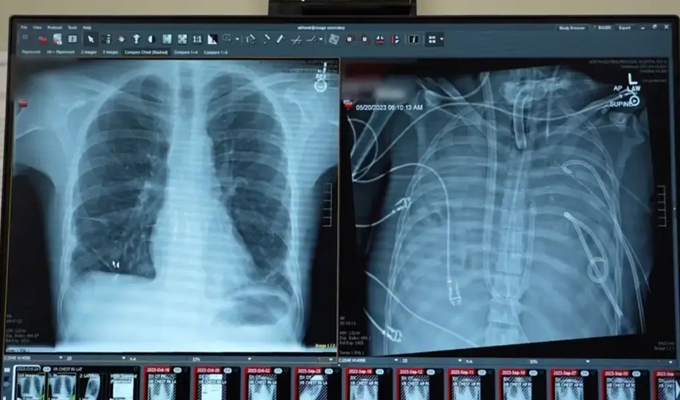

En los Estados Unidos, un hombre había sufrido daños irreversibles por complicaciones de la gripe. Por eso, se mantuvo sin pulmones hasta que la infección remitió lo suficiente para poder practicar el trasplante de pulmones requerido para salvarle la vida.

El hombre de 33 años permaneció 48 horas sin pulmones mientras esperaba a un trasplante bilateral a causa de una grave infección respiratoria.

El paciente sufría una infección pulmonar masiva (causada por influenza y neumonía bacteriana) que no respondía a tratamientos y estaba provocando un fallo multiorgánico.

Los cirujanos decidieron retirar ambos pulmones infectados para eliminar la fuente de la sepsis y permitir que el cuerpo se recuperara antes del trasplante.